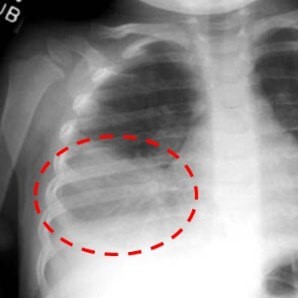

Микоплазму пневмония определяют при помощи прослушивания легких, рентгенологического исследования и ряда лабораторных анализов:

Диагностика заболевания